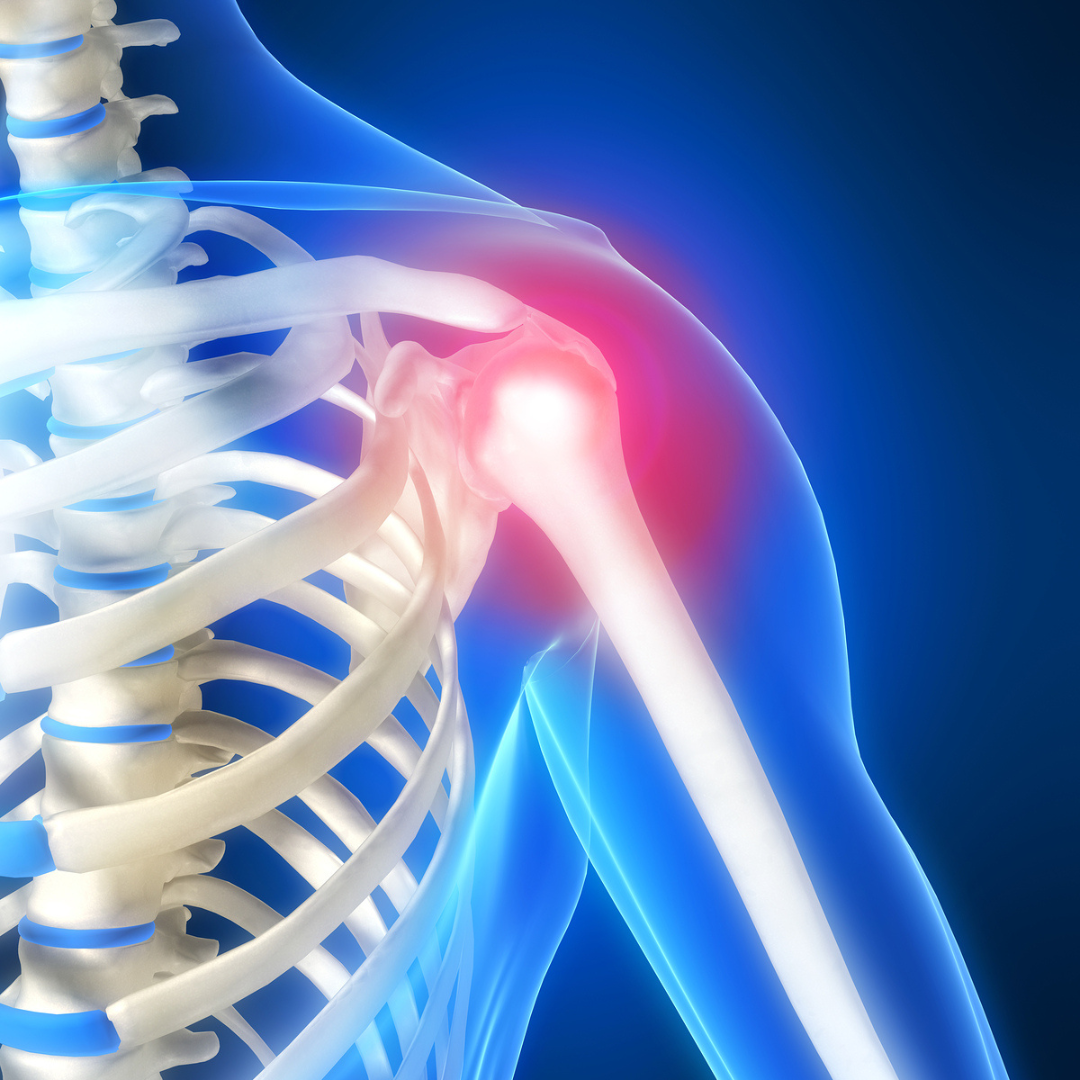

When chronic shoulder pain and limited mobility begin to interfere with daily activities, total shoulder replacement surgery offers a life-changing solution. Whether you’re suffering from shoulder arthritis, a fracture, or a rotator cuff injury, this advanced procedure can restore strength, reduce pain, and help you return to an active, independent lifestyle.

Q: Why Would Someone Need a Total Shoulder Replacement?

A: Total shoulder replacement is typically recommended for patients with arthritis in the shoulder joint who have not responded to conservative treatment options like physical therapy, medications, or injections.

Common symptoms include:

- Persistent shoulder pain that limits everyday activities

- Moderate to severe pain even while resting

- Weakness and reduced range of motion in the shoulder